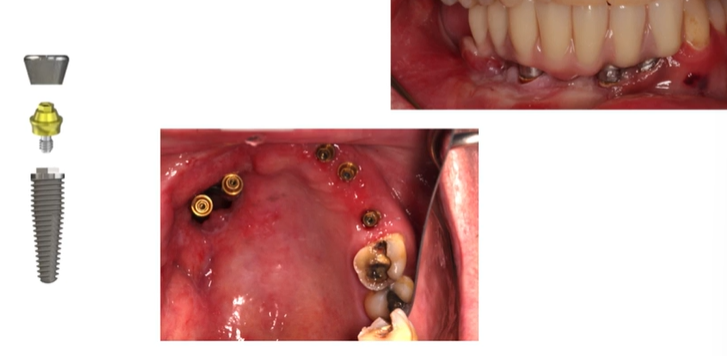

Implant Treatment

Planning phase → Surgery (period of osteointegration healing - 4-6 months in maxilla and 3-6 months in mandible) → Restoration → Maintenance

Clinical stages – single crown

Planning → Surgical phase → Healing for osseointegration

→ Primary impressions (using a special tray) → Open tray implant, pick up secondary impression → Fit

Clinical stages - bridge

→ Primary impressions, open tray implant pick up secondary impression → Verification jig, jaw reg → Try in → Fit